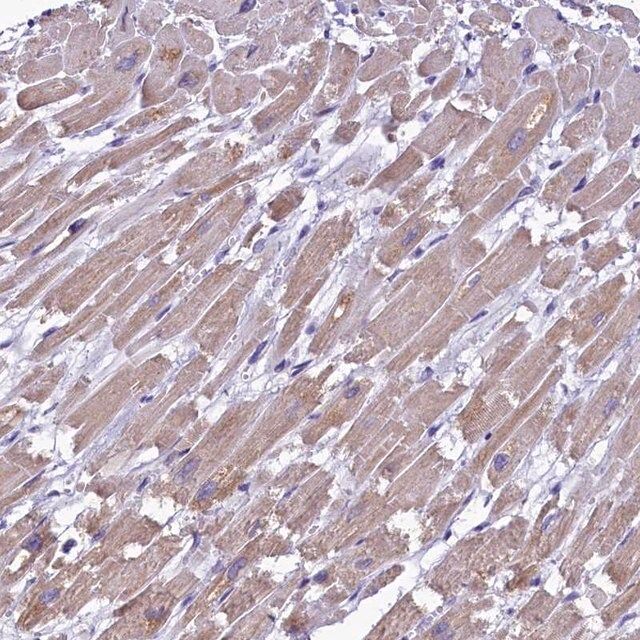

isocitrate dehydrogenase 3 (NAD+) alpha recombinant protein epitope signature tag (PrEST)

- IHC tissue array of 44 normal human tissues and 20 of the most common cancer type tissues.

| technique(s) | immunoblotting: 0.04-0.4 μg/mL immunofluorescence: 0.25-2 μg/mL immunohistochemistry: 1:200-1:500 |